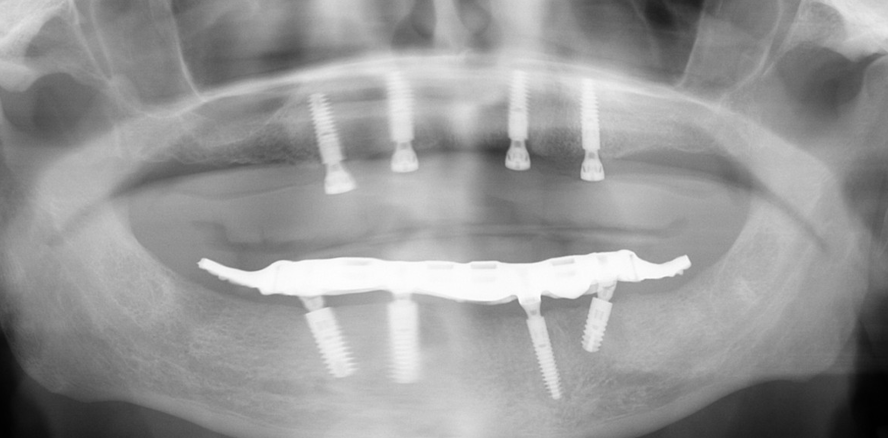

Die Fragestellung zur Implantatanzahl im Oberkiefer oder Unterkiefer ist oft sehr patienten- und behandlerspezifisch zu betrach-ten. Für Kostenträger ist die Frage oft von übergeordneter Relevanz. Für den Praktiker stellt sich die Frage nach der Umsetzbarkeit. Zudem sind auch das Knochenangebot und dessen Qualität für die Anzahl der Implantate und auch der Implantattypus maßgebend. Folgender Beitrag zeigt ein Fallbeispiel mit drei Implantaten, sechs Jahre in situ.

Ein immer viel diskutiertes Thema ist die Implantatanzahl beim All-on-X-Konzept. Diese ist von vielen Faktoren abhängig. Zu nennen sind der Implantattyp, der Implantatdurchmesser und die Implantatinnengeometrie. Im Weiteren sind die Knochenqualität und -quantität zu betrachten. Auch spielt die Gegenbezahnung zum All-on-X-Kiefer eine entscheidende Rolle, sodass hier keine einheitliche Linie für den Oberkiefer erkennbar ist. Es gelten in der Regel vier bis sechs Implantate als ausreichend. Im Unterkiefer sind es in der Regel vier. Wie dargestellt, reichen bei diesem Implantatsystem auch drei Implantate aus.